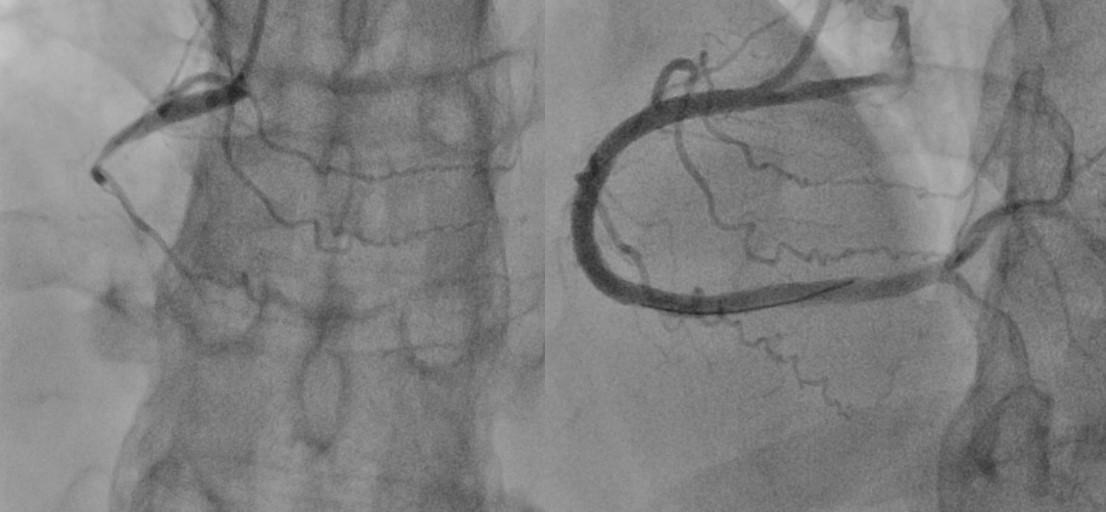

Budassi: Le CTO PCI sono sicuramente procedure complesse, costose, gravate da un più alto tasso di complicanze ma con il progredire delle tecniche il successo procedurale è aumentato notevolmente negli ultimi anni.

Stazi: Certamente, la percentuale di successo delle ricanalizzazioni percutanee delle CTO (CTO PCI) è andata progressivamente aumentando, sia per il miglioramento dei materiali a disposizione che per la maggior competenza acquisita dagli operatori ed attualmente si attesta intorno all’ 85-90%, nei centri migliori, e intorno al 60-80% nei registri più ampi e quindi più indicativi del mondo reale. Senza entrare nello specifico sono ormai disponibili differenti tecniche (anterograda, dissezione-rientro, retrograda) che devono tutte essere parte del bagaglio tecnico degli operatori.